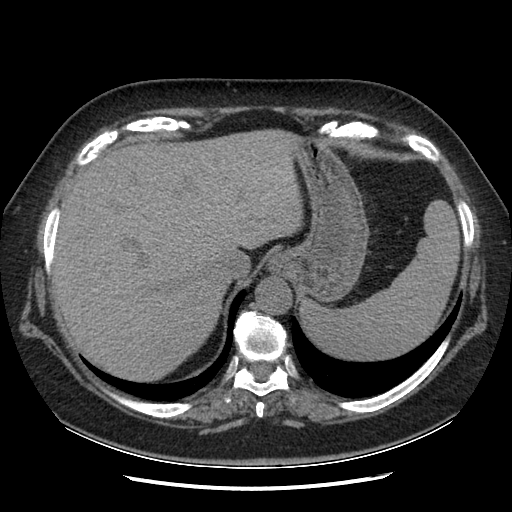

Original NATIVE CT scan (input)

Full window (WL 1023.5, WW 4095 β†’ Low βˆ’1024, High +3071)

Actual HU range: [-160.0, 240.0]